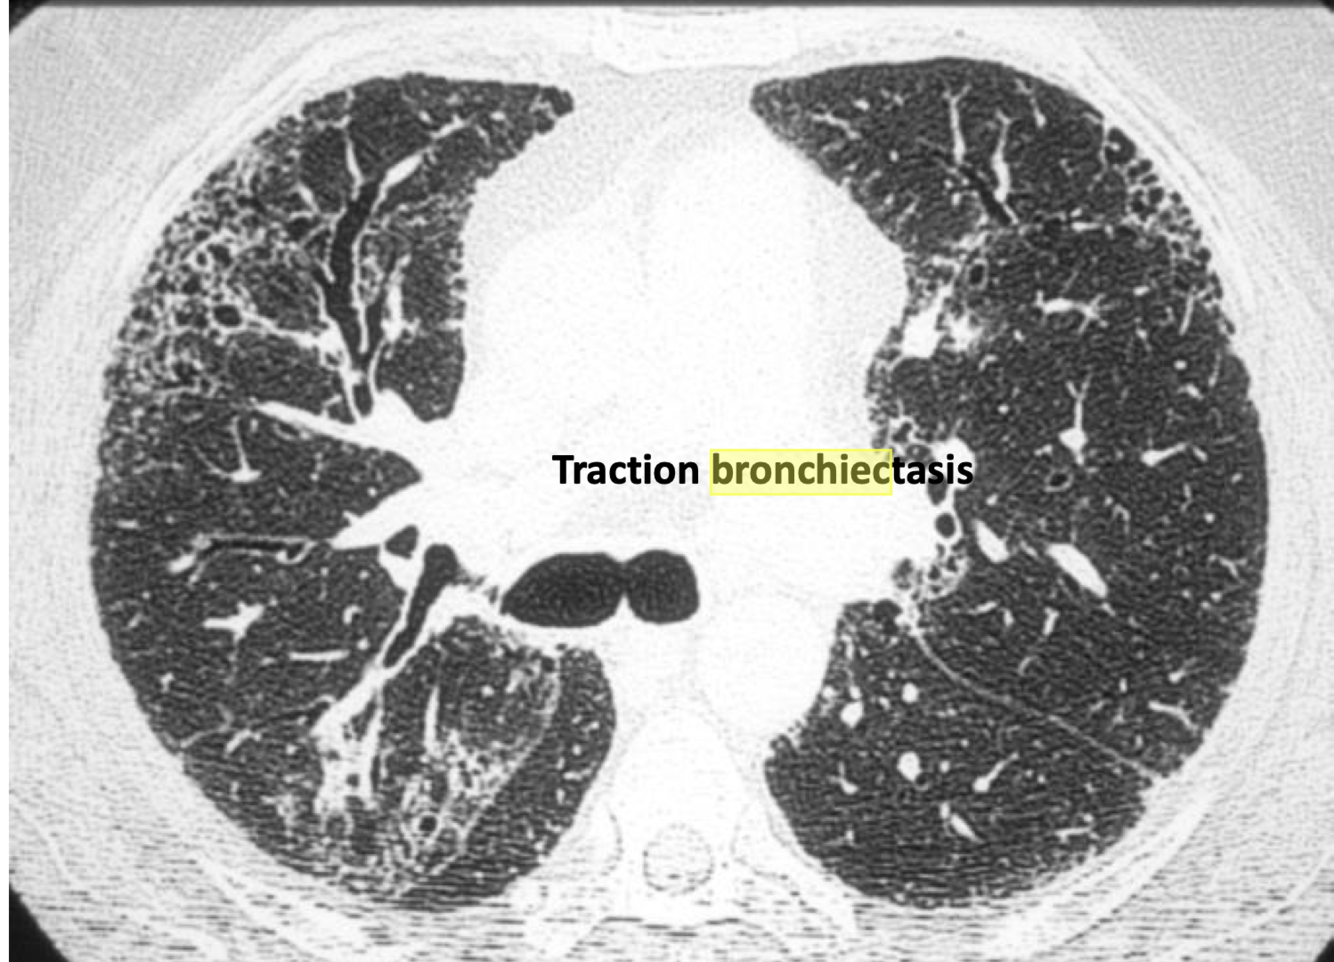

Traction bronchiectasis-

airway dilated because lungs are pulled by fibrotic lung

Traction bronchiectasis- airways dilated because pulled by fibrotic lung * This is a different etiology, seen in ILD, & managed differently*

- pulmonary fibrosis with periphery reticular pattern.